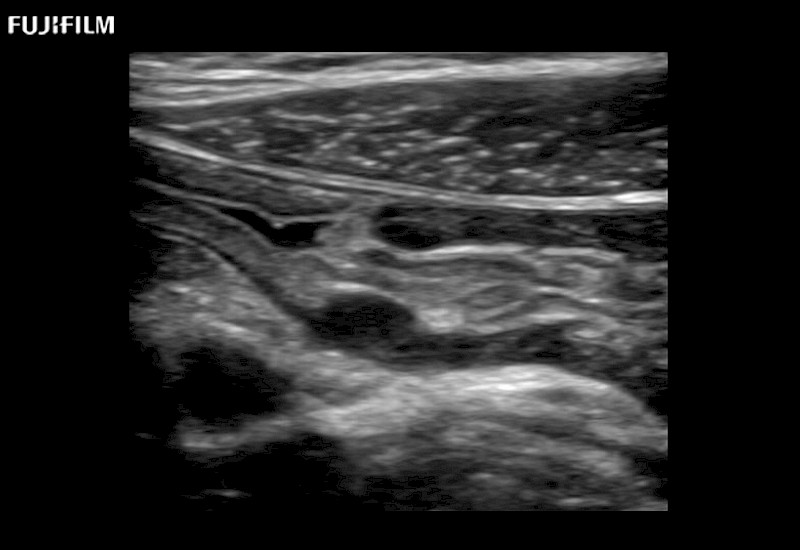

Extraordinary high-resolution digital imaging

- Exceptional near and far-field resolution

- Instant feedback on tumor margin delineation

- Valuable information to guide tumor resections

- Exceptional near and far-field resolution

- Instant feedback on tumor margin delineation

- Exceptional near and far-field resolution

- Exceptional near and far-field resolution

- Instant feedback on tumor margin delineation

- Exceptional near and far-field resolution

- Instant feedback on tumor margin delineation

- Exceptional near and far-field resolution

- Instant feedback on tumor margin delineation

- Exceptional near and far-field resolution

- Instant feedback on tumor margin delineation

- Valuable information to guide tumor resections

- Exceptional near and far-field resolution

- Instant feedback on tumor margin delineation

- Valuable information to guide tumor resections

- Exceptional near and far field resolution

- Instant feedback on tumor margin delineation

- Valuable information to guide tumor resections

- Exceptional near and far-field resolution

- Instant feedback on tumor margin delineation

- Valuable information to guide tumor resections

- Exceptional near and far field resolution

- Instant feedback on tumor margin delineation